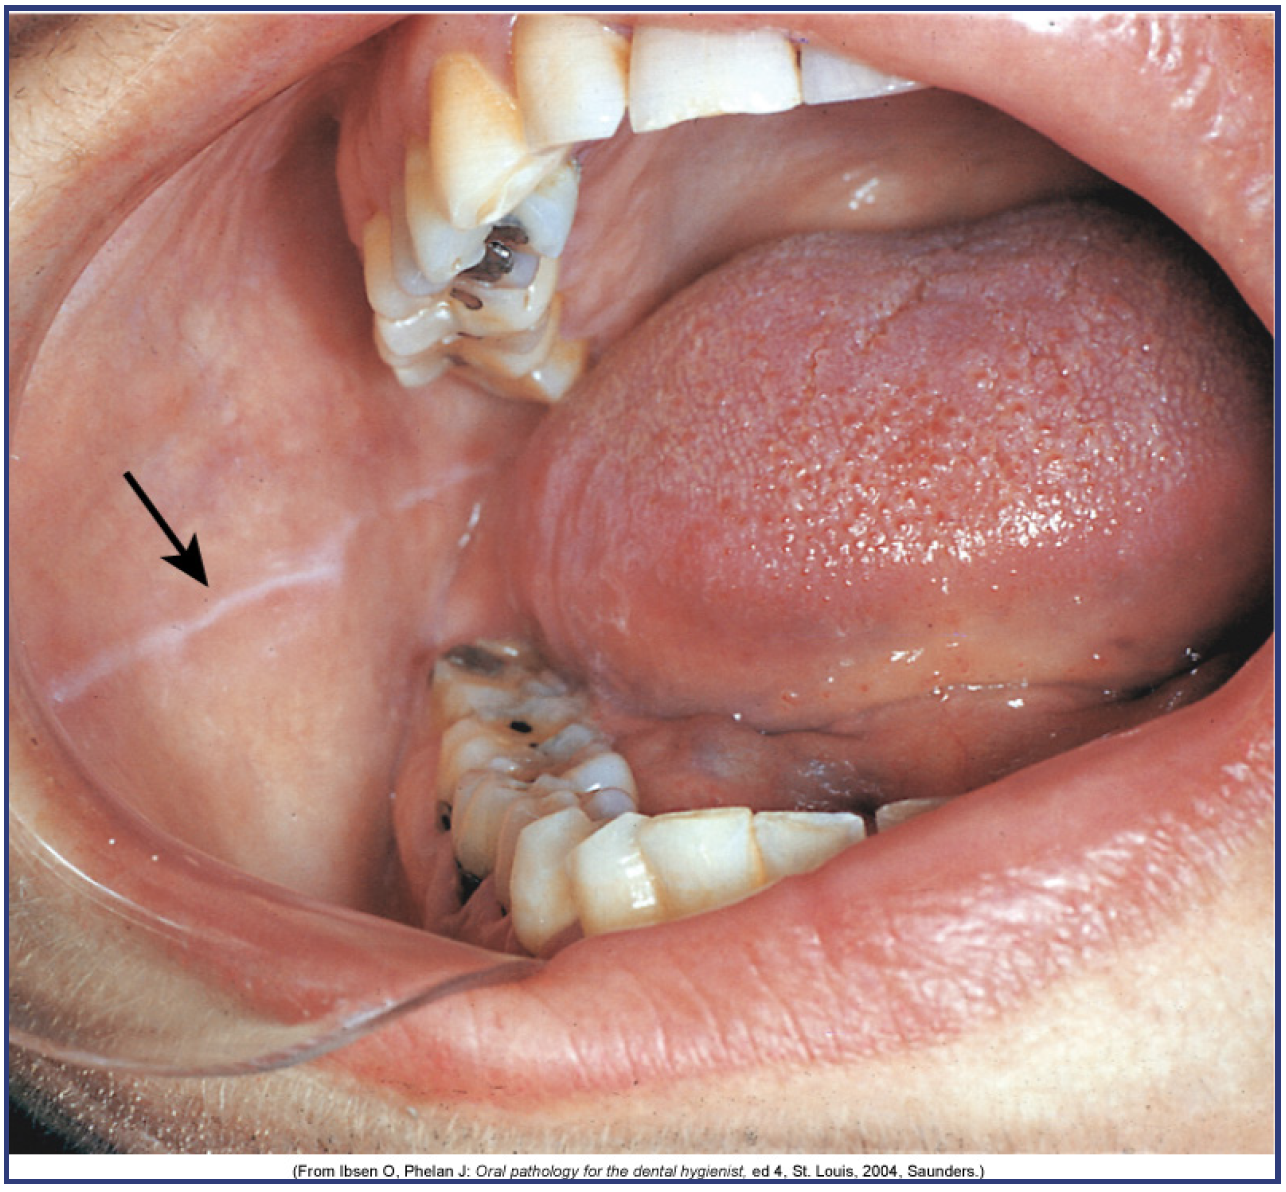

• Linea Alba: A raised white line of keratinized tissue on the buccal mucosa that runs parallel to the line of the occlusal plane.

Figure 7 – Linea Alba (Courtesy of Modern Dental Assisting, 10th Edition, Bird et al, Figure 10.7). Example of a linea alba in the patient’s cheek.

Figure 7